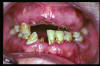

CM Edentulismo parcial, restos radiculares y caries